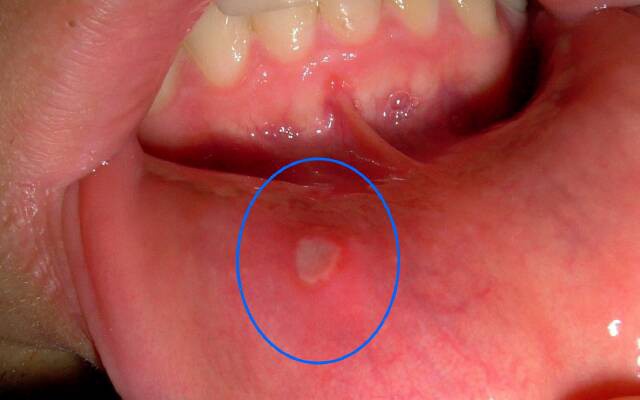

Афтозний

У дорослих проявляється утворенням невеликих ранок круглої форми – афт, мають білий або жовтуватий відтінок з червоною окантовкою. Іноді виникає при механічних пошкодженнях передній частині ротової порожнини: на губах, щоках, кінчику язика. Більшість медиків схиляються до думці, що етимологія афтозного стоматиту вірусна, називаючи причинами аденовіруси, герпетичну інфекцію.

Як виглядає стоматит — фото

Невелика підбірка фото: як виглядає стоматит у роті, на язиці або губі.